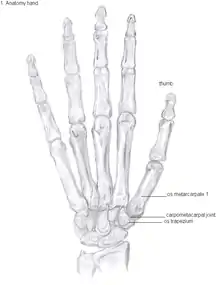

Anatomy

The CMC1 joint is a synovial joint between the trapezium bone of the wrist and the metacarpal bone at the base of the thumb. This joint is a so-called saddle joint (articulatio sellaris), unlike the CMC joints of the other four fingers which are ellipsoid joints.[16] This means that the surfaces of the CMC1 joint are both concave and convex.

Because of its specific shape, the CMC1 joint allows a wide range of motion of the thumb. Movements possible in this CMC1 joint are:[17]

This high mobility is due to the little intrinsic osseous stability of the joint. This causes the CMC1 joint to be more unstable compared to the CMC joints of the other fingers.[18] Because of this instability, the joint is more susceptible to be damaged.[12] To remain stable the CMC1 joint has to rely on the surrounding ligaments for support. These ligaments provide the ability to subject high pressure loads, particularly during pinch and grasp manoeuvres.[19]

16 ligaments surrounding the CMC1 joint are identified, which give strength and stability to the joint. Of these ligaments, the deep anterior oblique ligament, also known as the palmar beak ligament, is considered to be the most important stabilizing ligament.[20]